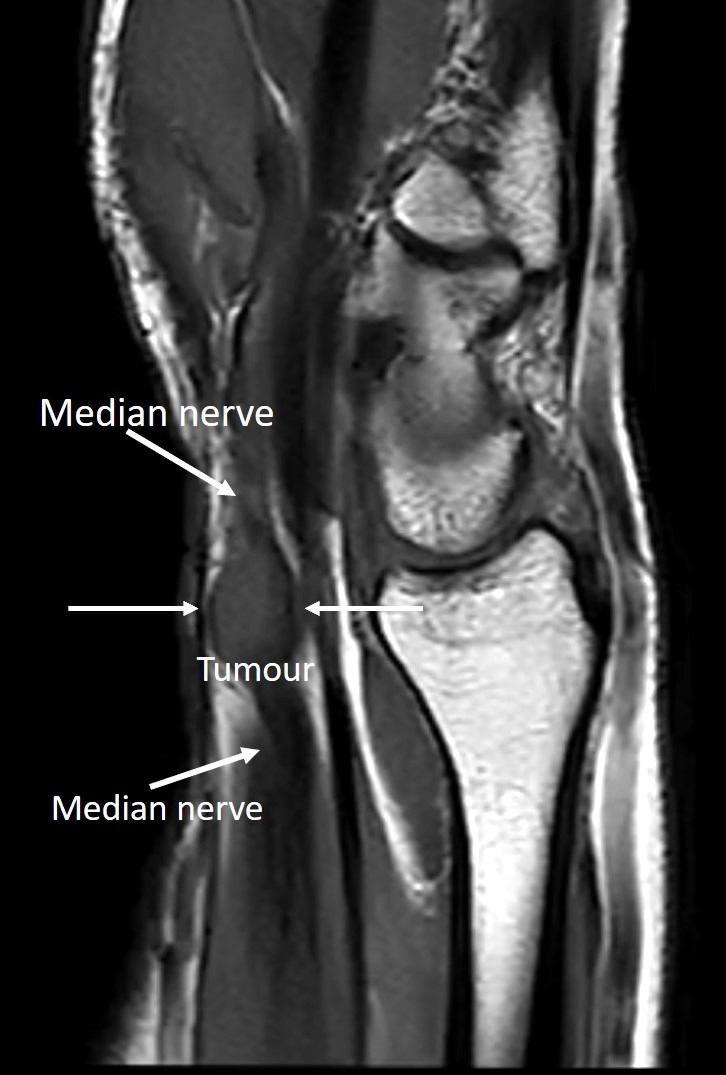

Enucleation of the median nerve tumour under WALANT: a case report

A case of a median nerve tumour (schwannoma) located in the distal part of the forearm, which was enucleated from the nerve under local anaesthesia (WALANT), without the use of a tourniquet on the arm to obtain a bloodless surgical field, is presented. To the best of the authors’ knowledge, this is the first described case of nerve tumour surgery under this anaesthesia. It shows that operation of nerve tumours can be performed under WALANT, without deteriorating of patients’ safety and surgeons comfort. The authors believe that presentation of this case can be interesting for hand surgeons and will encourage them to extend the scope of operations performed under WALANT.